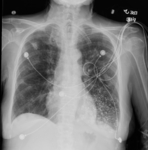

Acute aspiration

Bronchoscopy showing barium aspiration in a lung transplant patient in the right mainstem bronchus after a barium swallow study

From the collection of Dr Kamran Mahmood